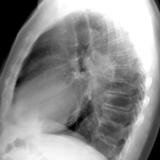

RLL Collapse  1 Lateral

Date: 02/28/2004

Views: 3187